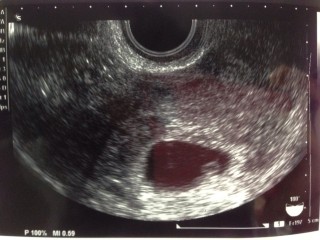

ピコピコ動いているのが赤ちゃんです。赤ちゃんは1人の様ですね。おめでとうございますと先生に言われ一安心しました。診察前はとてもドキドキしましたが一瞬でエコーで確認でき想像していたより早い心拍には驚きましたがとても感動しました。

排卵日がほぼ確実なので6w5dで間違いないだろうとのこと。ただ、胎嚢約2cm、赤ちゃん約5mmと少し小さいそうで2週間後に再診予定。2週間後には大きく育ってくれてるといいな(^^)

流産の可能性は低いと言われました。 元気に育ってね(o^^o)